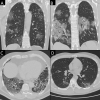

Figures